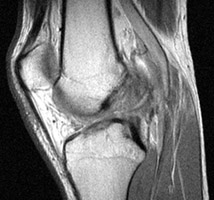

Sagittal T2 weighted and proton density images which reveal complete tear of the ACL with mild increase in marrow signal in the adjacent osseous structures. The bone bruises, as evidenced by increased signal within the marrow, is likely caused by anterior subluxation of the tibia at the time of tear of the ACL accompanied by impaction of the middle portion of the lateral femoral condyle against the posterior portion of the lateral tibial plateau. Signal intensity abnormalities are probably secondary to edema, hemorrhage, and microfracture.